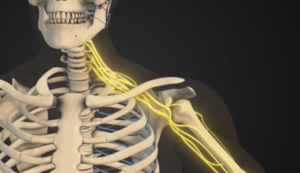

首の回旋ができない原因 ❸ 斜角筋の動きが硬い

斜角筋は、前斜角筋・中斜角筋・後斜角筋と3つあります。これらの斜角筋が動かなくても首の回旋は制限されます。

- 前斜角筋・中斜角筋を緩めたい時は胸鎖関節の下で第1肋骨の隙間に停止するので、胸鎖関節を緩めることがポイントです。

- 2つ目のポイントは、第1肋骨と鎖骨の胸骨端にコピー用紙1枚の隙間ができるように操作することです。

- 後斜角筋を緩めたい時は、第2肋骨外面に停止している部分、ちょうど第2肋骨が鎖骨の外1/3の下を通過するあたりの緊張をとる事がポイントです。多くの場合、ここで第2肋骨と鎖骨が粘ったようになっているので、こちらもコピー用紙1枚の隙間ができるように操作しましょう。